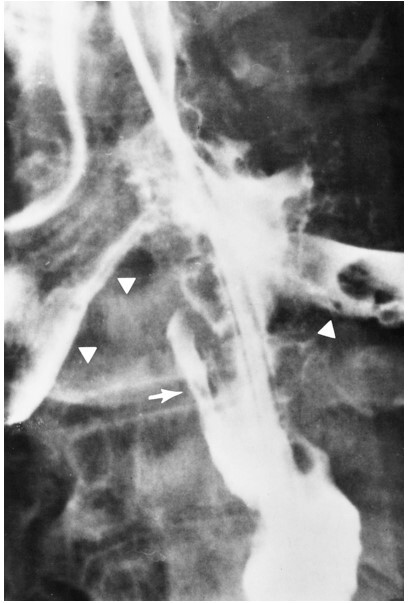

What pathology is seen here?

A

Tracheoesophageal Fistula

What are the radiographic signs of a Tracheoesophageal Fistula?

-Connection of the fistula between airway and esophagus

-Large dilation of the esophagus